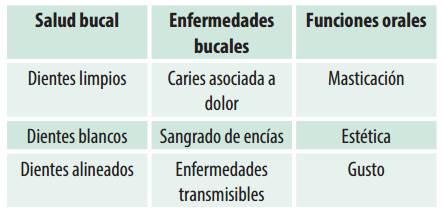

Considerando la categoría “conocimiento” se encontraron los siguientes resultados sobre salud, enfermedad y funciones orales (cuadro 2).

El conocimiento que los participantes de la investigación tenían sobre salud-enfermedad bucal se relacionó a la blancura, alineación correcta y limpieza de las piezas dentarias. Las enfermedades bucales más conocidas fueron caries dental, sangrado de las encías y enfermedades infecciosas transmisibles como HIV y sífilis. Las principales funciones orales alteradas según sus relatos fueron la masticación, la estética y el gusto a partir de la situación de consumo habitual de SPA.